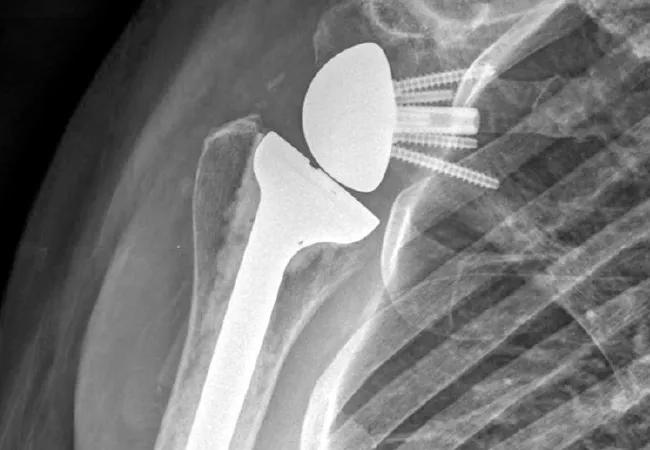

Figure 1. (A) Anteroposterior radiograph of a painful right total shoulder arthroplasty that underwent revision for humeral implant malpositioning. Preoperative workup for infection was negative, but intraoperative frozen section tissue specimens demonstrated acute inflammation concerning for infection, and (B) an antibiotic-impregnated cement spacer was placed. Intraoperative cultures subsequently produced P. acnes, and following antibiotic treatment, the patient ultimately underwent (C) reimplantation with a reverse total shoulder arthroplasty due to glenoid bone loss and rotator cuff deficiency.